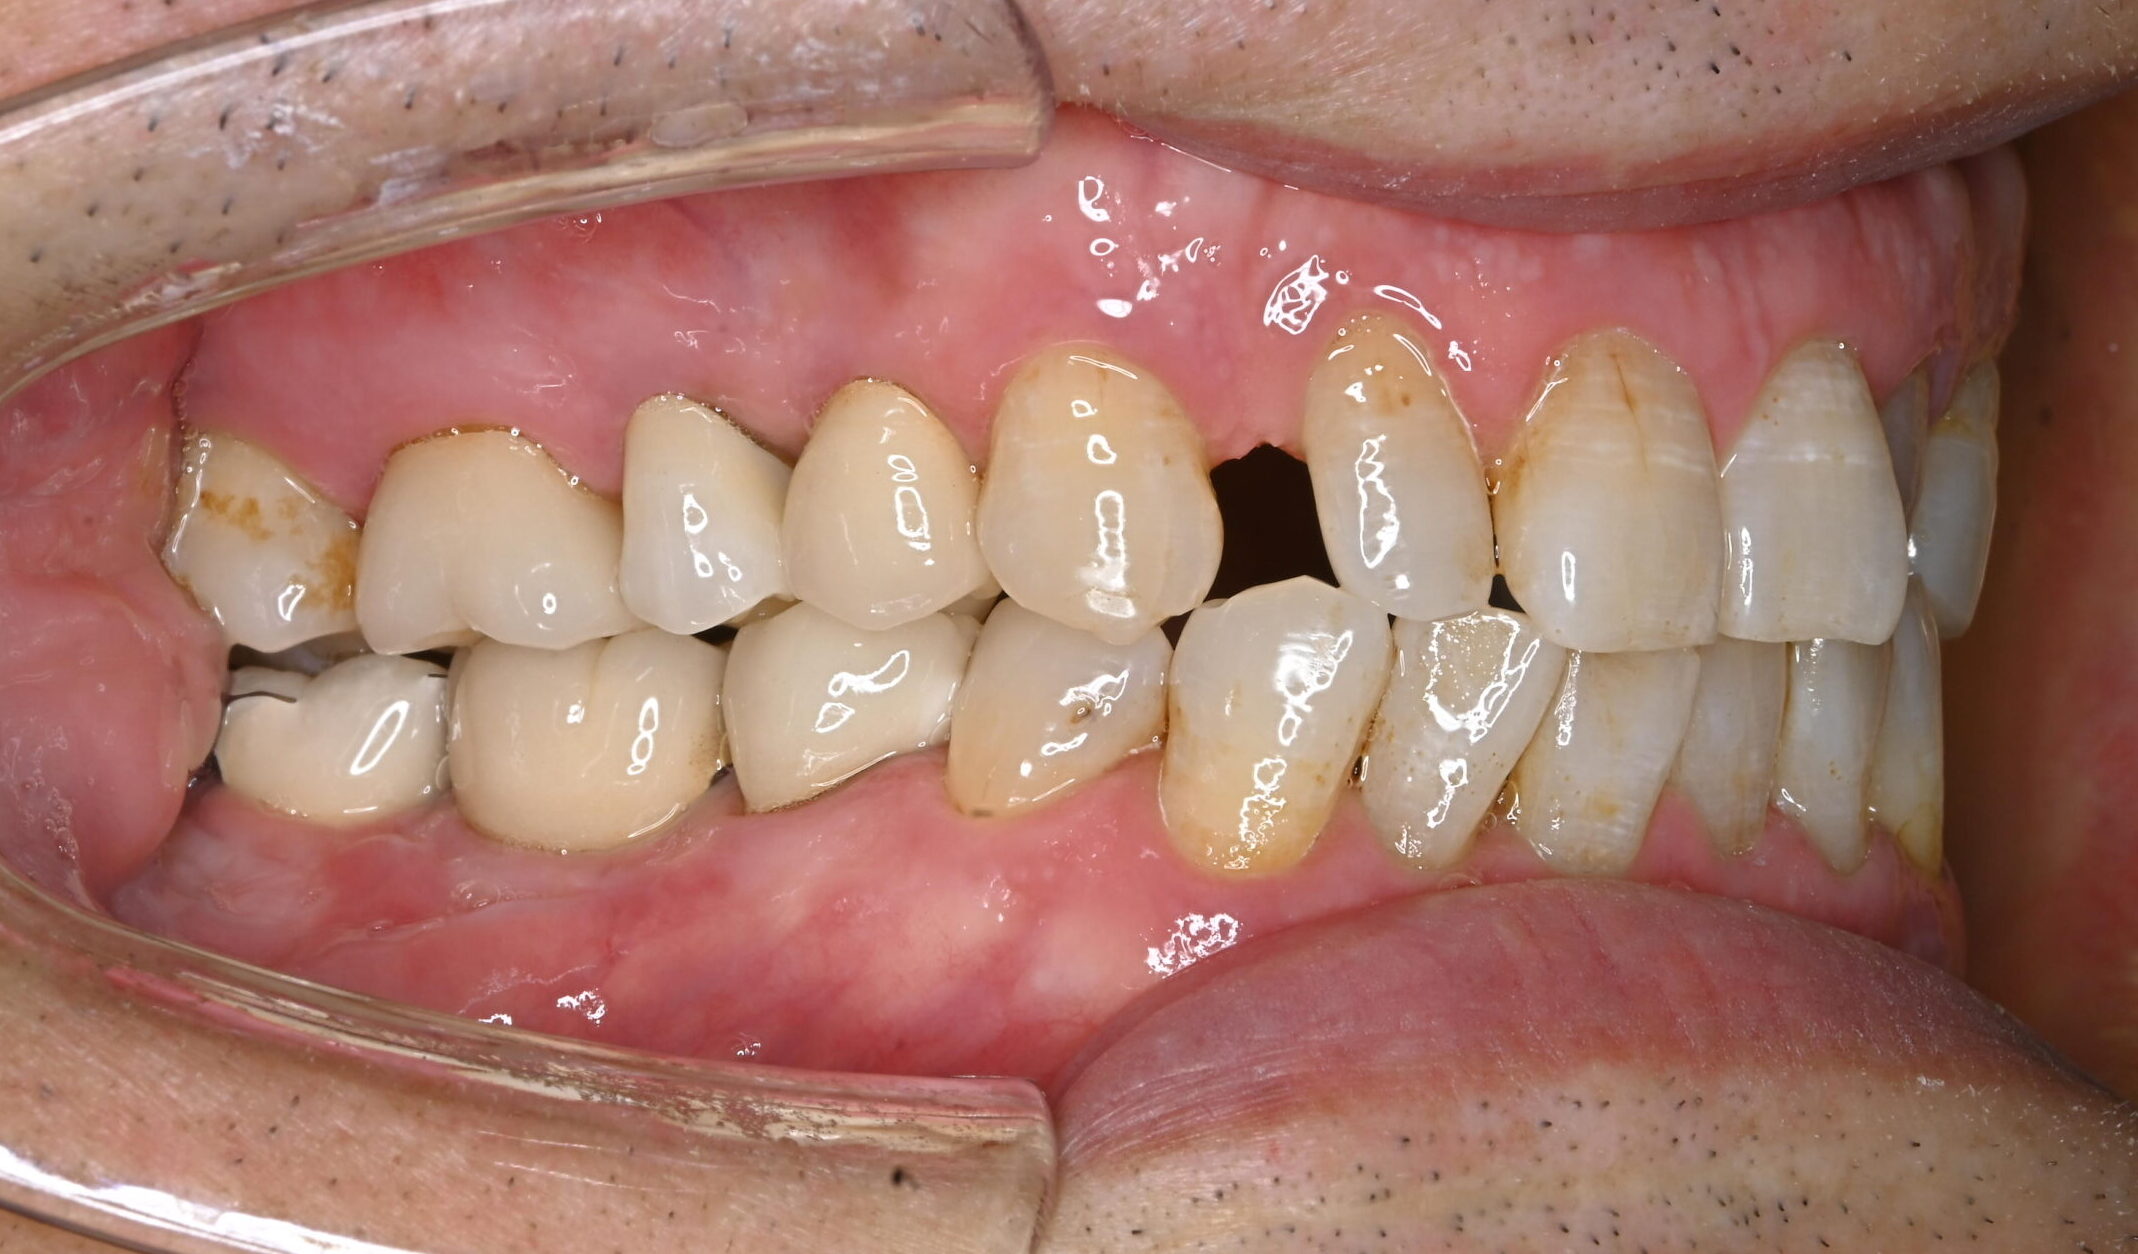

左右の下の奥歯が欠けたという主訴で来院されました。

診断の結果、下顎左右6番の根尖性歯周炎と2次虫歯が認められました。

どちらの歯も状態が悪く保存的処置が望めませんでした。患者さんとの相談の結果、抜歯しインプラントを埋入することになりました。

まず右下6番の抜歯、インプラント埋入手術、上部構造の装着を行い、次いで左下6番の治療を右下同様に進めました。